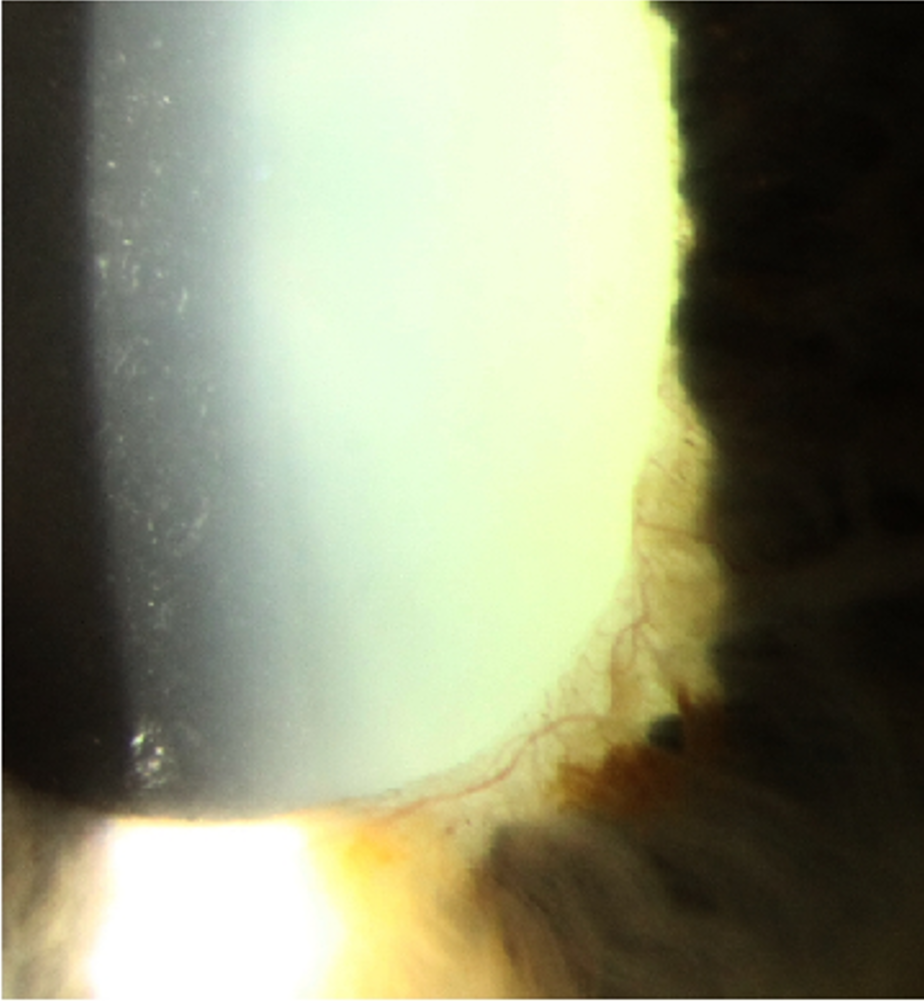

Gonioscopy shows the presence of blood vessels in the angle. Over time, with disease progression, peripheral anterior synechiae can form and narrow the anterior chamber angle.

Goniophotos right eye

More info

Goniophotos left eye